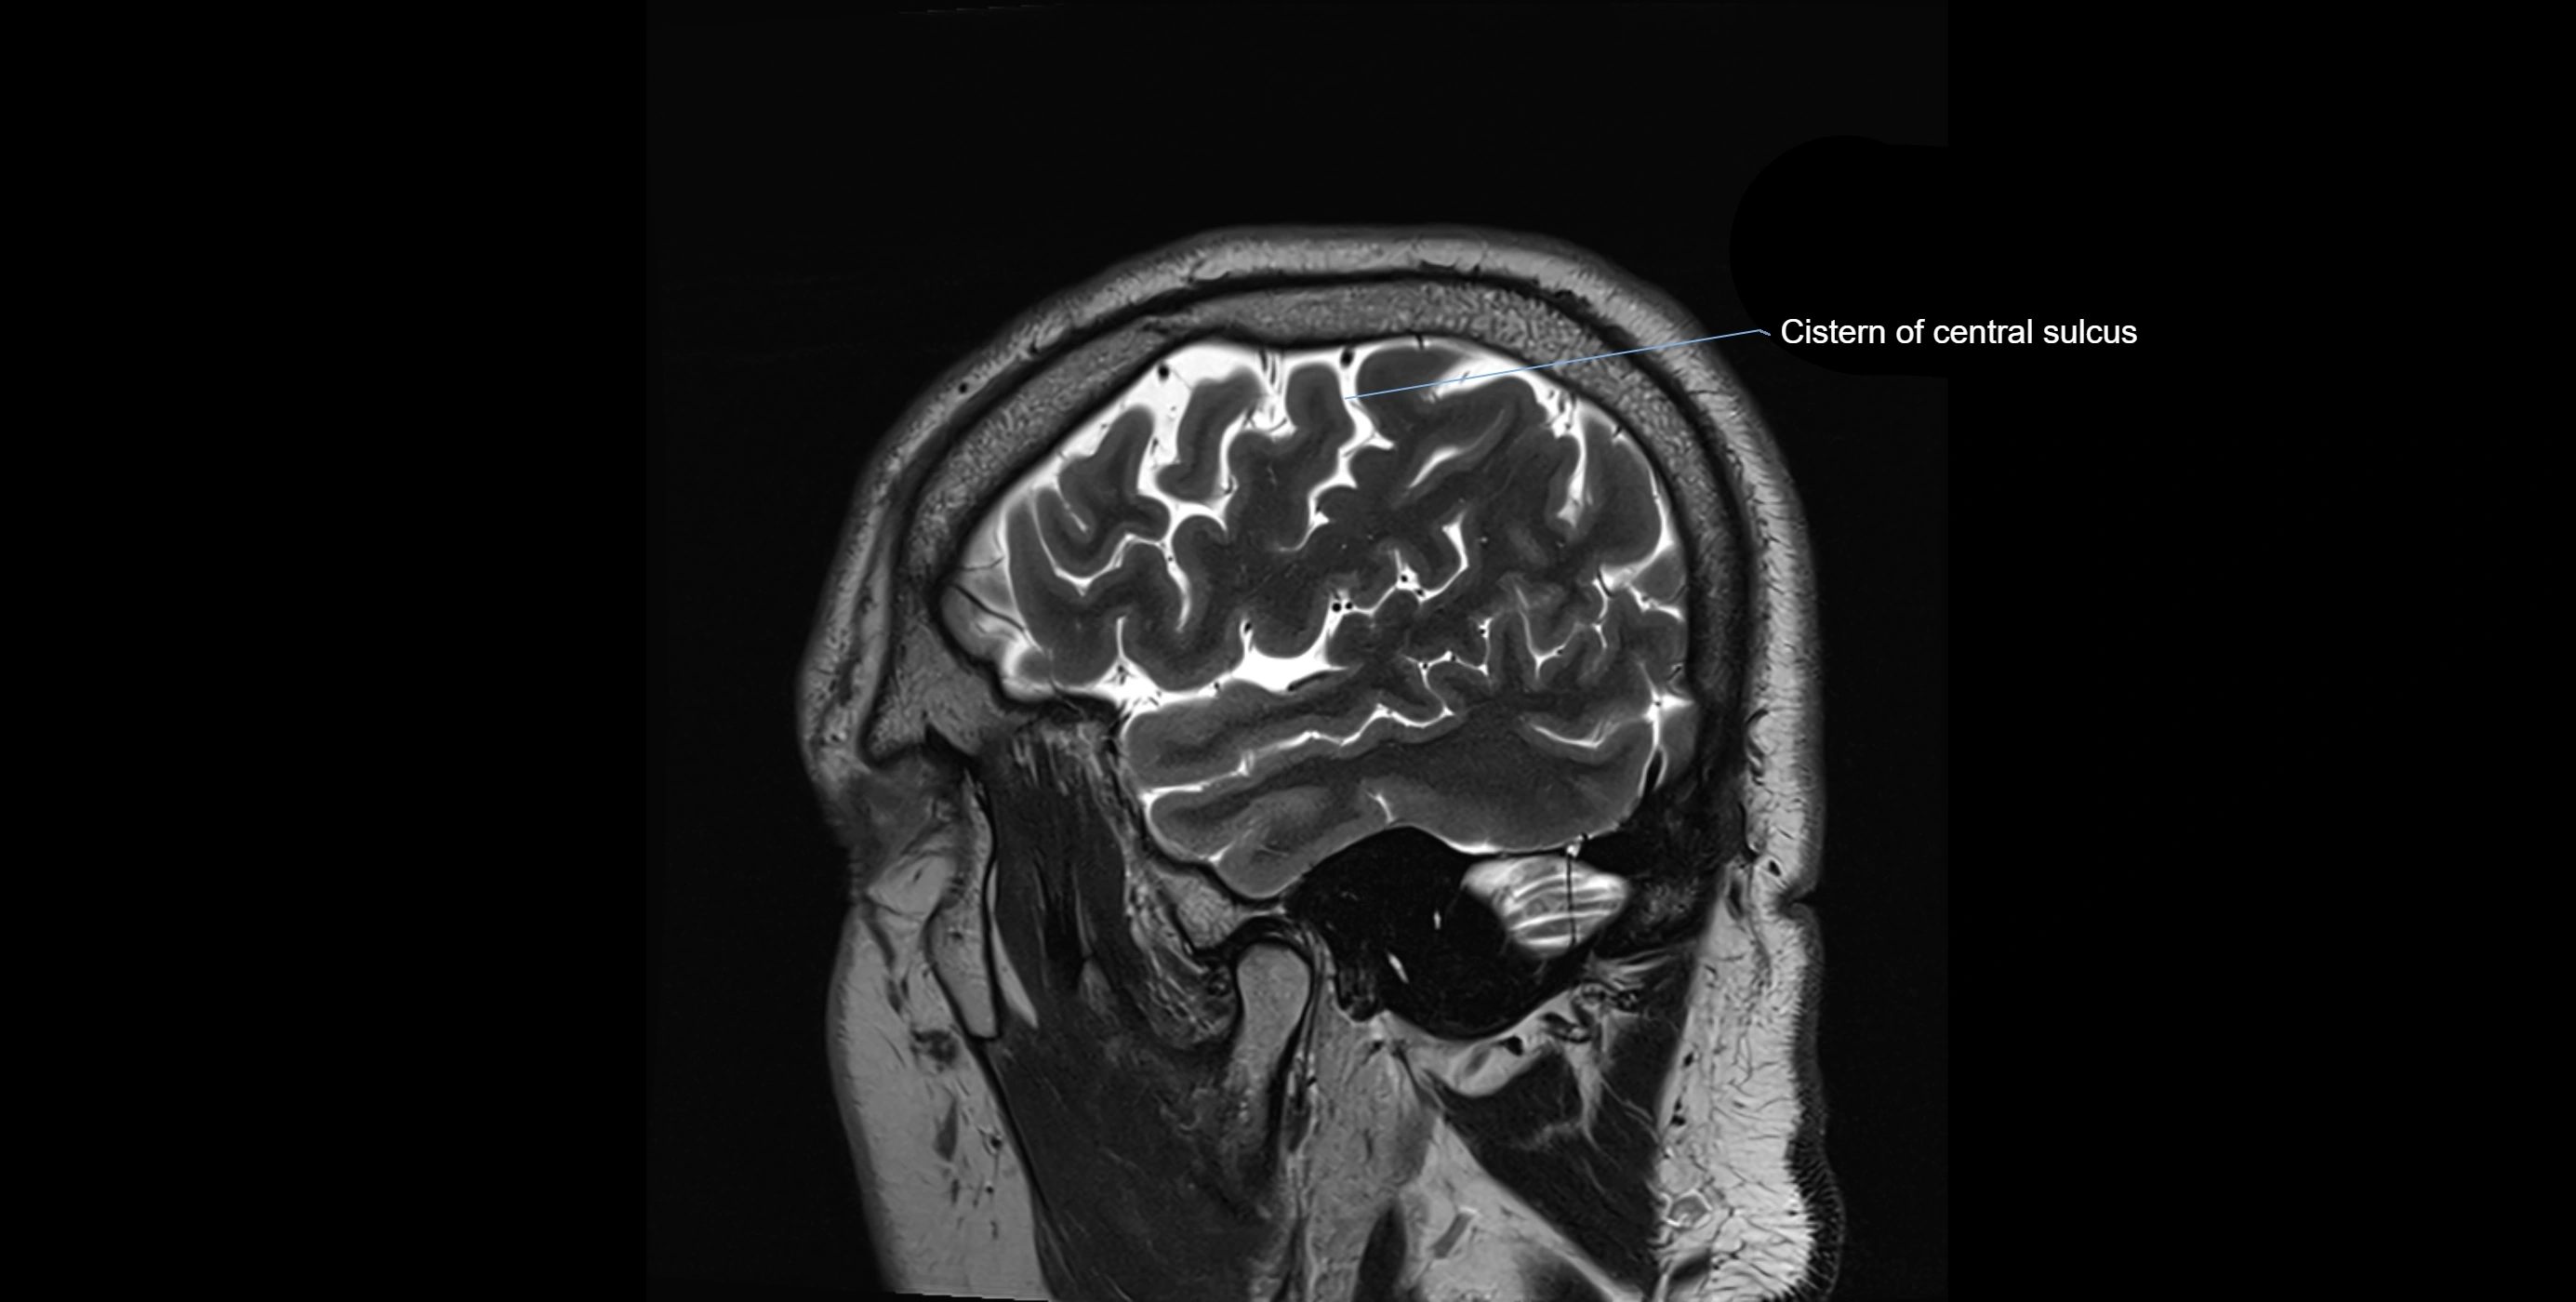

MRI images

image